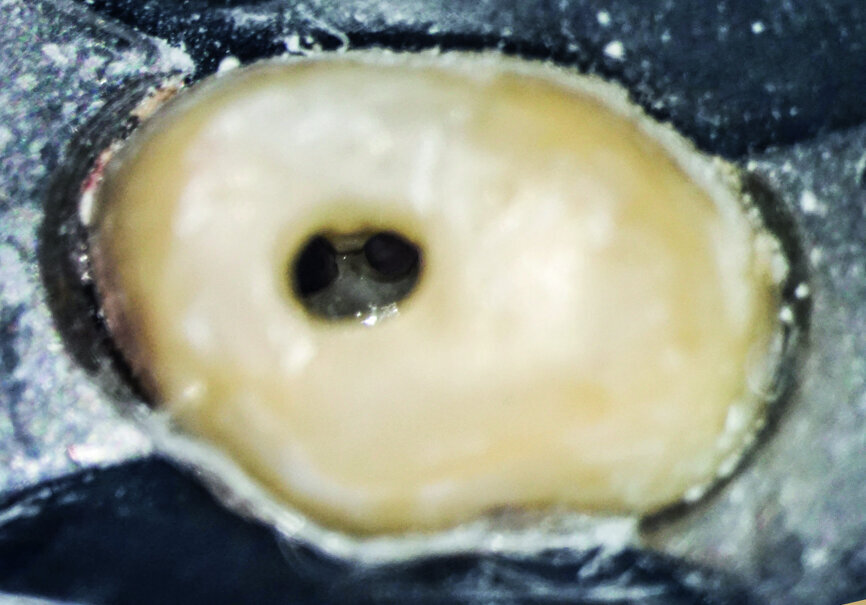

After isolation of the tooth (Fig. 3), an access cavity was created using high-speed diamond burs and ultrasonic tips (Figs. 4–8). Pre-flaring in the coronal and middle thirds was done with the HyFlex EDM 25 instrument (at a torque of 4 Ncm and a speed of 500 rpm). It is a proven fact that pre-flaring allows an increase in the instrument size that binds in the root canal, irrespective of the discrepancy between the size of the file and anatomical diameter. [19–21] Afterwards, canal scouting was performed using an ISO size 10 stainless-steel K-file up to working length. Upon establishing the working length, with the help of an apex locator, the 10/05 EDM file (glide path file) was used up to working length (at a torque of 3 Ncm and a speed of 300 rpm). Subsequently before finishing the preparation with the 25 EDM file, the 20/05 EDM (preparation file) was used to full working length (at a torque of 3 Ncm and a speed of 400 rpm). At this point, the working length was confirmed again with an ISO size 20 NiTi K-file. Root canal shaping was completed with the 25 EDM file, which was inserted to full working length (at a torque of 3 Ncm and a speed of 400 rpm; Figs. 9–12).